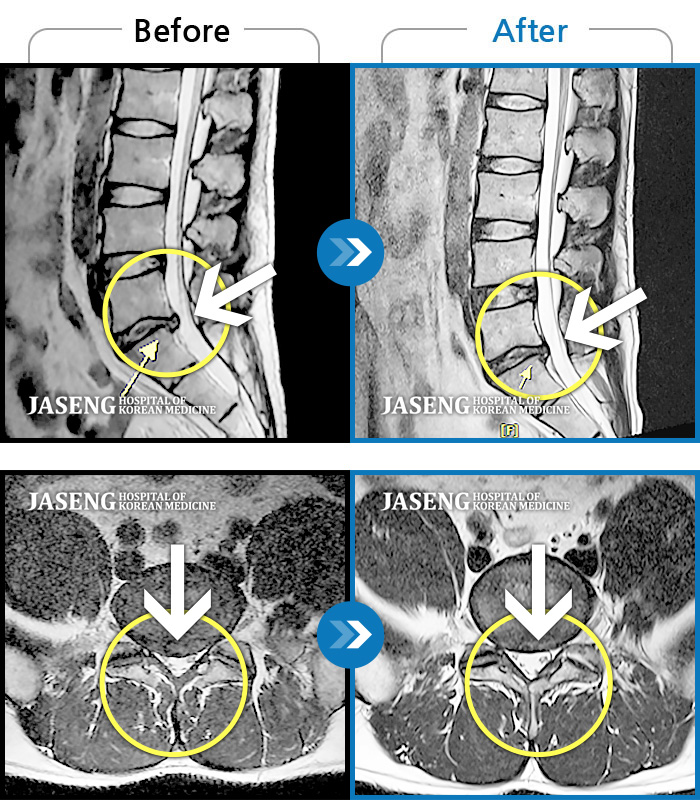

허리디스크

광주 · 장영우 원장

양측 허리부터 골반 묵직한 통증, 좌측 다리 외측까지 이어지는 당기는 통증으로 내원하셨습니다.

촬영시기

2503.04.01 ~ 2509.11.01

2025.09.22